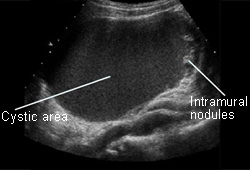

Ovarian cancer

Ovarian cyst with nodules on ultrasound

From the collection of Justin C. Chura, MD, Cancer Treatment Centers of America, Philadelphia, PA